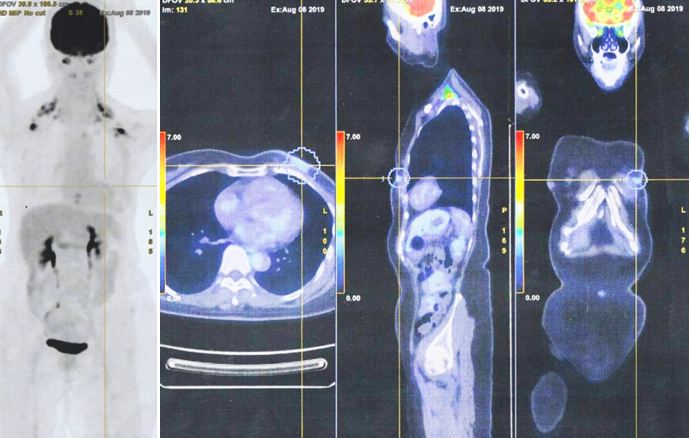

2. On 8 August 2019, I consulted an oncologist at a private hospital in Kuala Lumpur. A PET scan was done. The results indicated:

• Low grade FDG uptake seen at the post-operative inflammatory changes at left anterior chest wall. No hypermetabolic nodal or distant metastasis.

Due to the massive metastasis as shown in the PET scan done on 10 December 2021, Lucy had no choice but to proceed with chemotherapy. Indeed the cancer had spread extensively.

1. Amazing results of chemotherapy. Compare these three pictures –

Left: After surgery Lucy was on alternative therapy, refusing to undergo chemotherapy. The result was extensive metatastasis (middle). Right: Lucy has no choice but to go for chemotherapy. The outcome of 6 cycles of chemotherapy was just fantastic! In my 25 + years dealing with cancer patients, I have never seen such a great outcome of chemotherapy. Salute the oncologist! You rescued her!

In fact, the results were so unbelievable that one is tempted to ask if it is for real and not a fake? My answer is NO, detailed study of the PET scan results below are real! Study the images carefully – those before and after  chemotherapy.